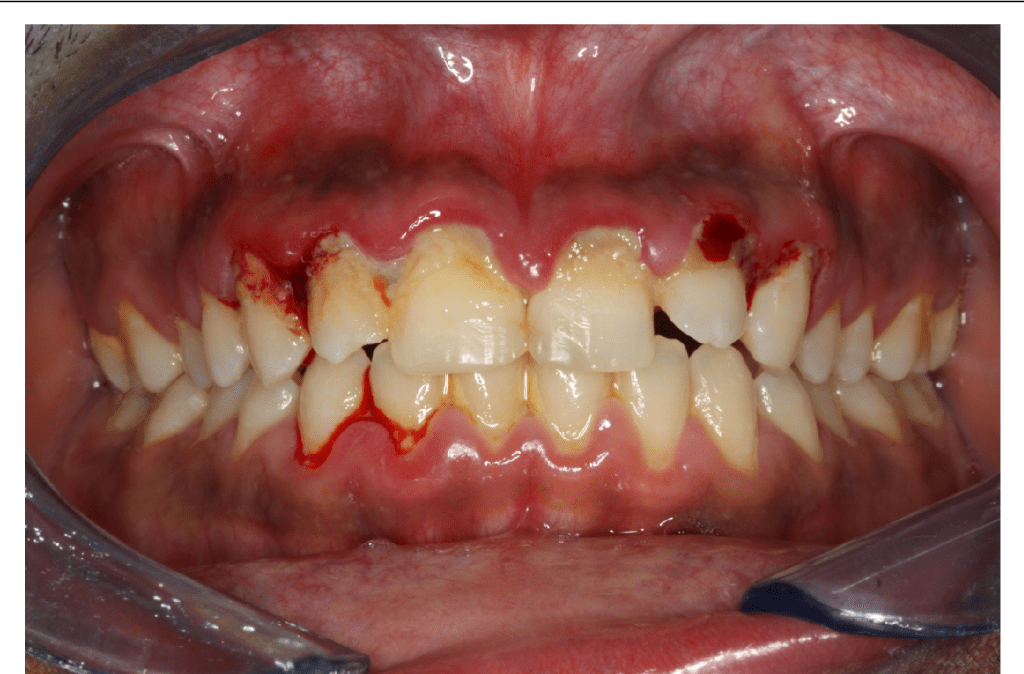

O sinal mais marcante é a necrose das papilas interdentais, frequentemente descrita como uma aparência em “cratera”, resultado da destruição tecidual localizada. Sobre essas áreas necrosadas, observa-se a formação de pseudomembranas acinzentadas ou esbranquiçadas, que recobrem as lesões e podem ser facilmente removidas, revelando um tecido subjacente intensamente dolorido e sangrante.

A dor é outro sintoma predominante, de caráter agudo e muitas vezes desproporcional ao estímulo, tornando atividades rotineiras, como a mastigação ou até mesmo a higienização oral, extremamente desconfortáveis.

O sangramento gengival ocorre de forma espontânea ou ao mínimo contato, refletindo o grau de inflamação e fragilidade vascular local.

Associado a isso, a presença de halitose fétida é quase constante, consequência da necrose tecidual e da atividade metabólica de microrganismos anaeróbios, sendo um sinal de alerta perceptível tanto ao paciente quanto ao profissional.